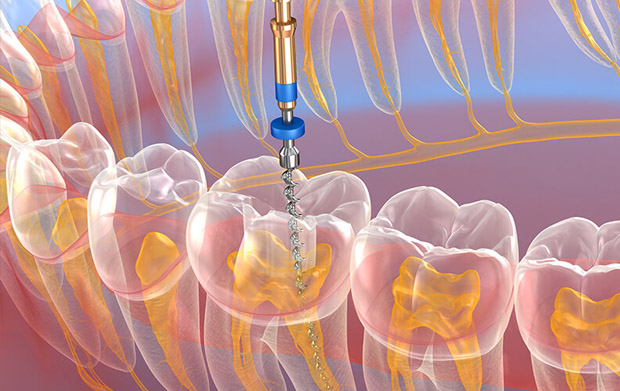

Endodontia (canal)